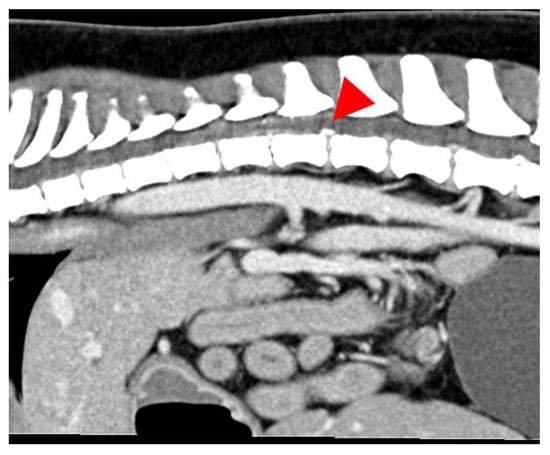

2.2. Diagnostic Imaging (CT and MRI)

2.3. Image Analysis